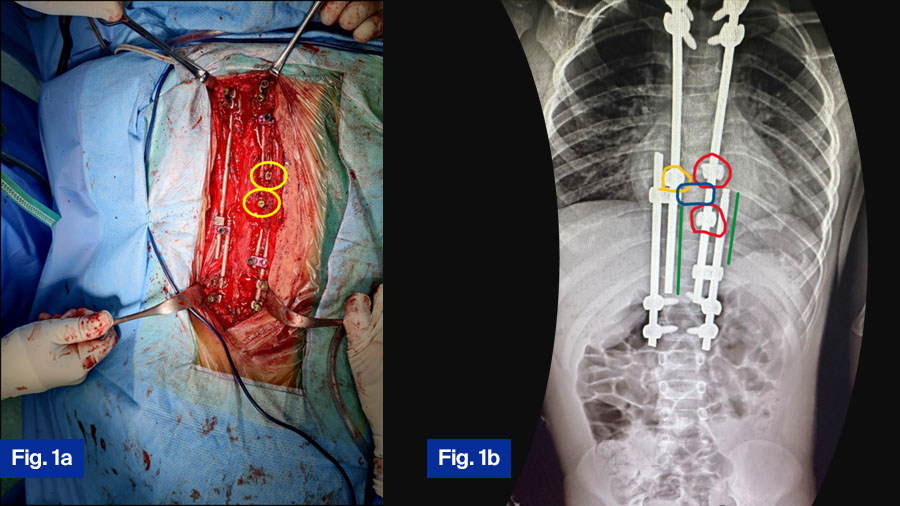

APC is a hybrid of guided growth and apex control through non fusion and reversed modulation-based philosophies for management of growing-spine deformity. It replaces the apical fusion of a traditional SHILLA with procedures (compression/distraction + medial translation + derotation) against primary drivers of curve progression, as shown in Figure 1, Figure 2.

- Using dominos with a hole equal to the rod diameter to overcome soft tissue impinging preventing rod sliding, shown in Figure 2.